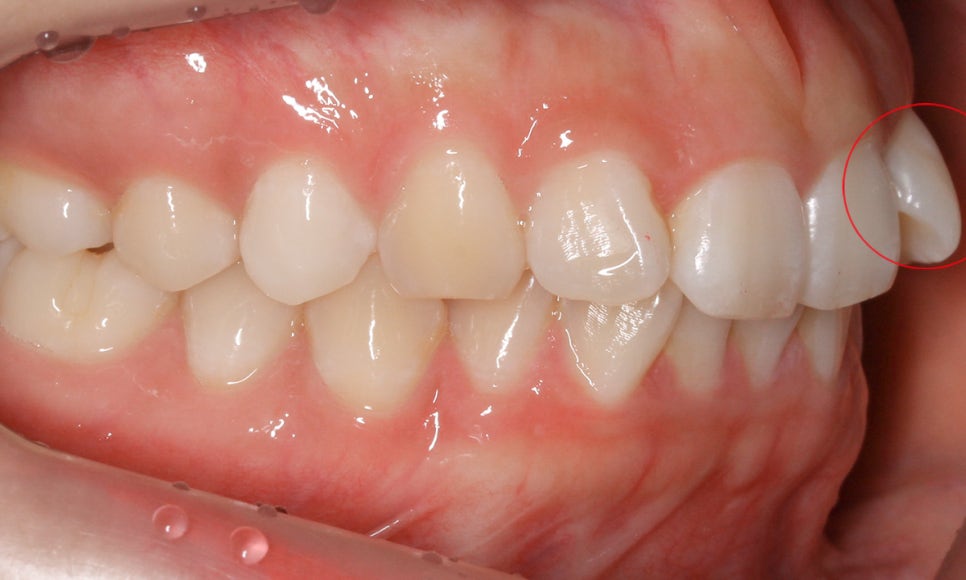

아래의 Case는 세라믹교정 을 진행한

앞니틀어짐 사례로 보시는 것처럼

상악 측절치의 각도가 틀어져 있어

교정이 필요한 모습인데요,

다음으로 상하악의 교합부를 보시면

상악과 하악이 교합되는 부위가

전치부 crowding으로 인해 약간

삐뚤거리는 모습을 확인할 수 있는데요,

특히 앞니틀어짐 있는 22번 측절치로 인해

전치부의 교합이 바르지 못한 모습입니다.

전치부의 돌출 정도를 파악할 수 있는

측면 사진을 보시면 측절치의 틀어짐으로 인해

미세하게 overjet(수평피개) 증상이 나타나는 모습으로

전치부 치열을 가지론하게 교정한다면

위와 같은 돌출감이 해결될 것으로 보입니다.